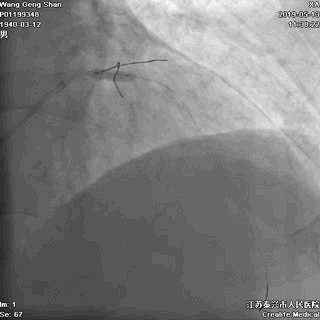

07 LM支架近段优化(POT)

左主干近段用大一号非顺应性球囊行高压扩张

IVUS评估,支架贴壁良好。